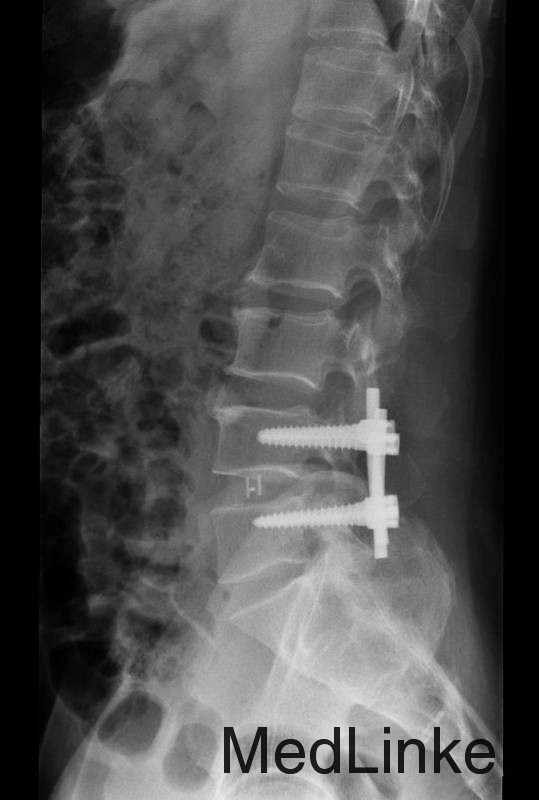

诊断 : 腰椎间盘脱出症,髓核游离 入院后完善检查,查无手术禁忌症后行腰椎后路椎板减压间盘切除椎间融合器椎弓根钉内固定术,术后患者左下肢疼痛缓解,术后支具保护下三天后拔除引流管后下地行走。